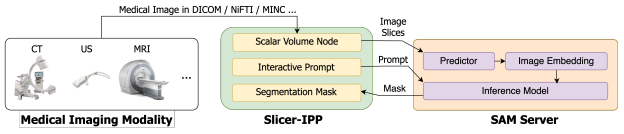

SAMM

Segment Any Medical Model, SAMM:这是一个结合了3D Slicer和SAM的医学图像分割工具,协助开发、评估和应用SAM。通过与3D Slicer的整合,研究人员可以使用先进的基础模型来分割医学图像。